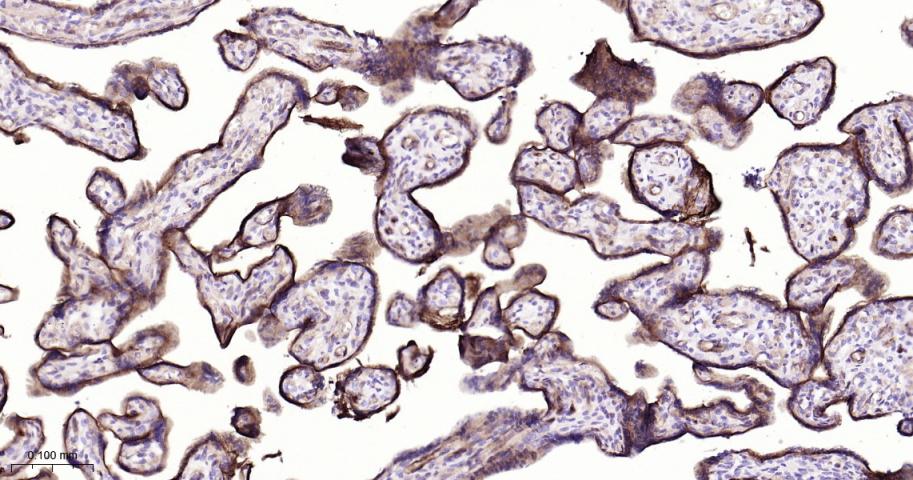

Paraformaldehyde-fixed, paraffin embedded Human Placenta; Antigen retrieval by boiling in sodium citrate buffer (pH6.0) for 15 min; The section was incubated with Integrin alpha 5 Monoclonal Antibody, Unconjugated (bsm-61357R) at 1:200 overnight at 4°C, followed by conjugation to the bs-0295G-HRP and DAB (C-0010) staining.